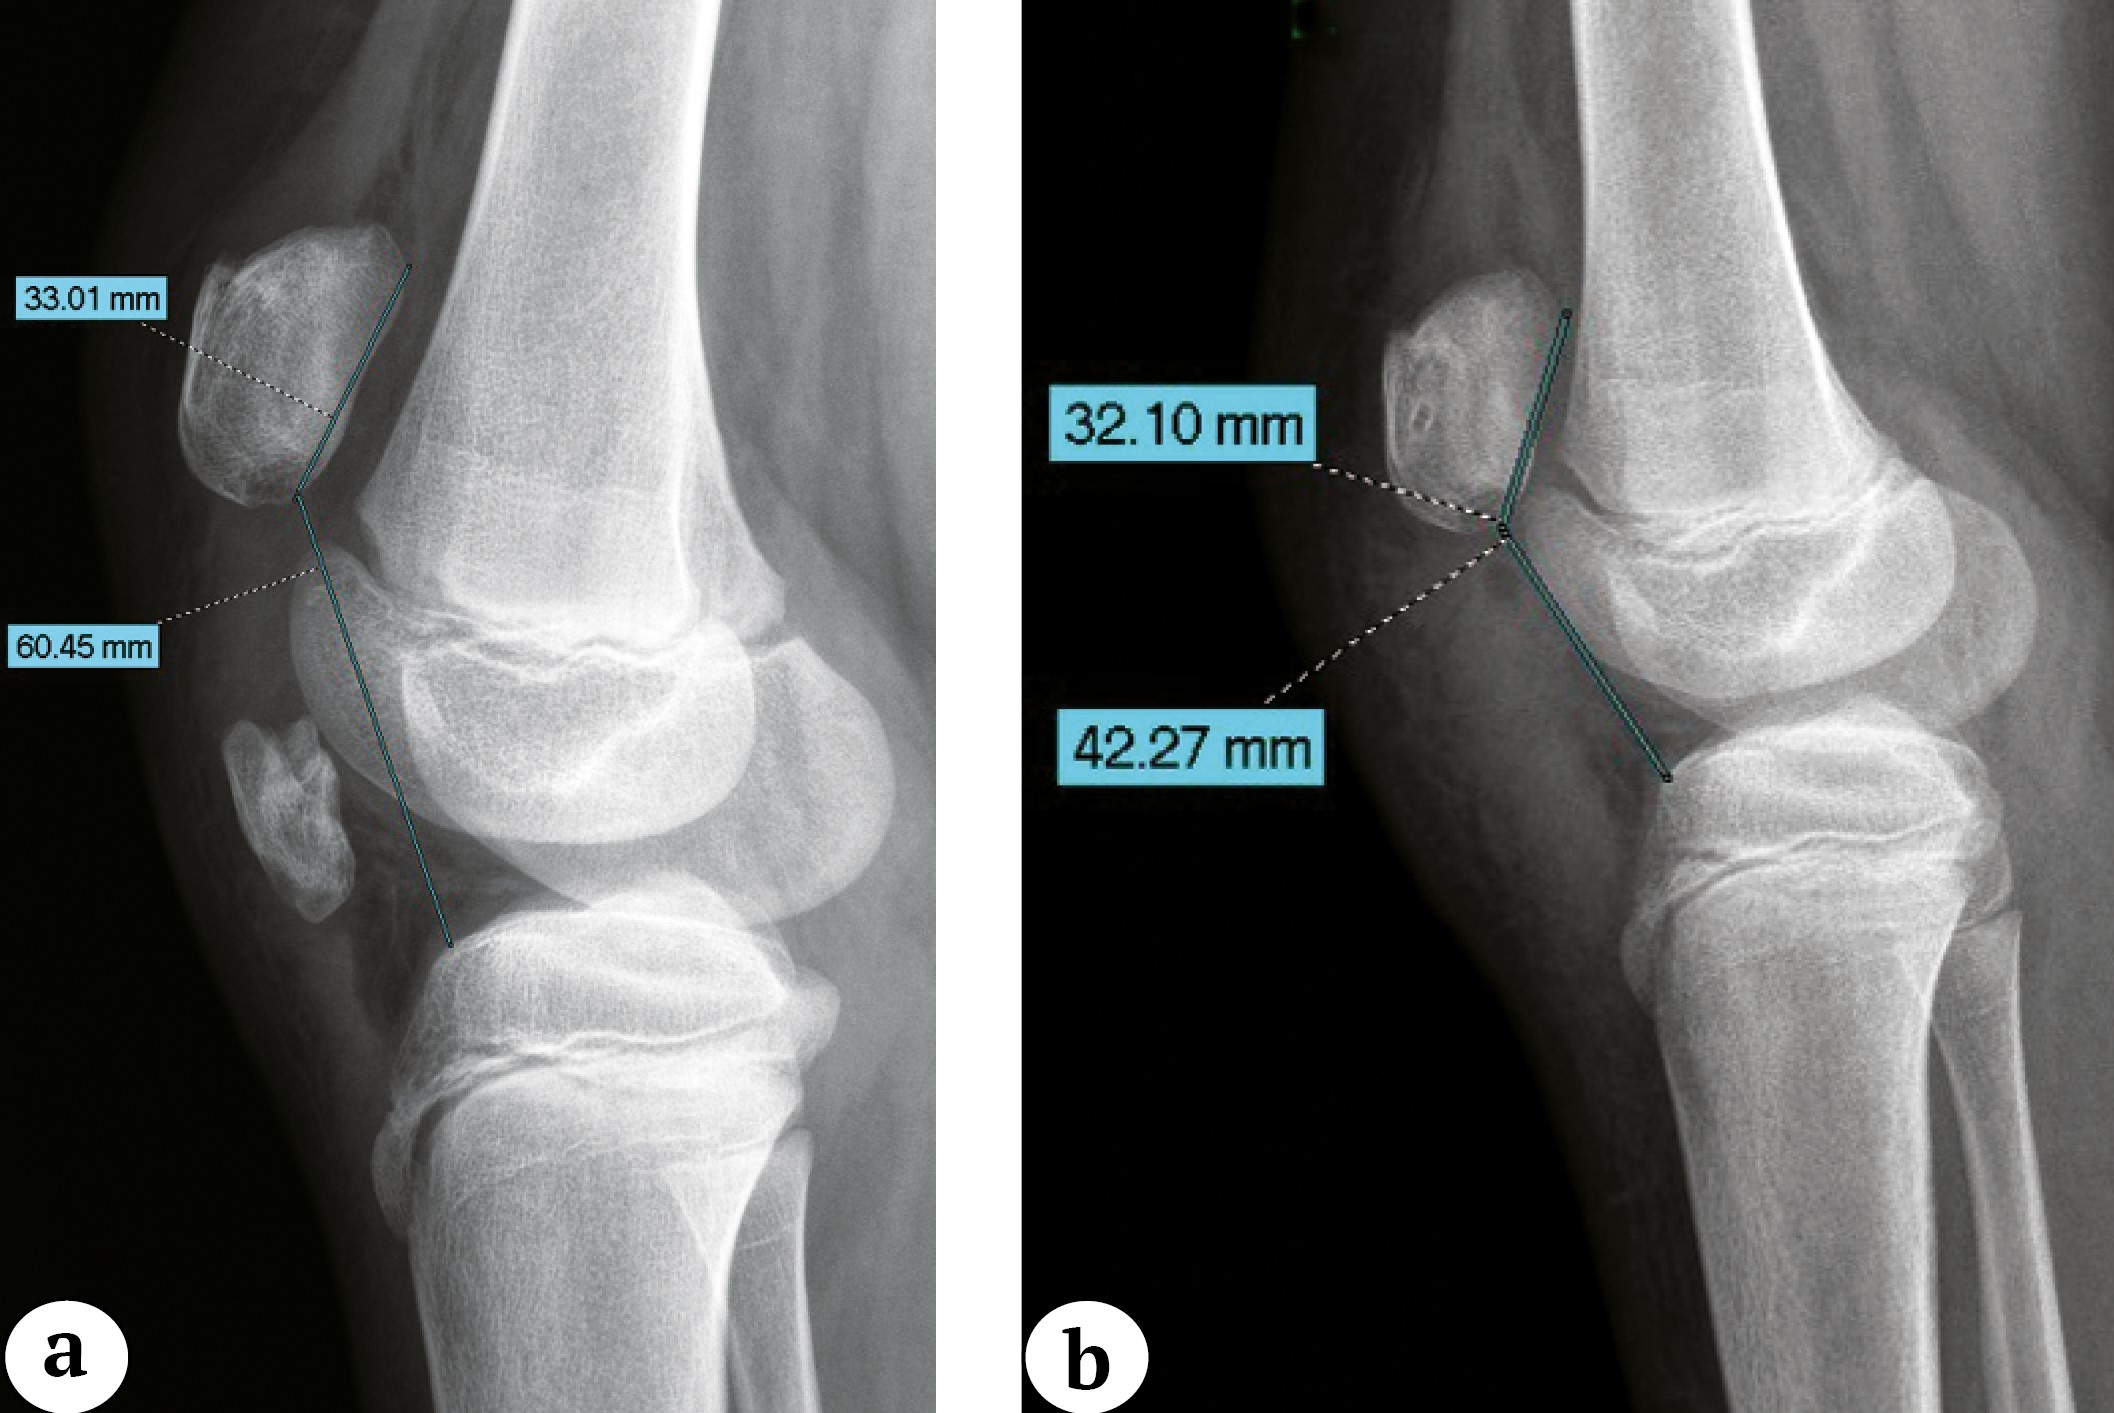

Лучевая картина. На рентгенограммах коленного сустава, выполненных в двух проекциях, у всех пациентов в проекции связки определялись костной плотности образования с неровным четким контуром в сочетании с высоким стоянием надколенника в прямой и боковой проекциях с увеличением индекса Caton – Deschamp (CDI) более 1,3 (рис. 1). Характеристика визуализируемых образований представлена в таблице 2.

Рис. 1. Рентгенограммы коленных суставов с односторонней оссификацией связки надколенника: а — прямая проекция, patella alta, оссификаты в проекции связки надколенника; b — боковая проекция, травмированная конечность, patella alta (индекс Caton – Deschamp — 1,8), оссификат в проекции толщи связки надколенника; c — боковая проекция, здоровая конечность

Figure 1. X-rays of the knee joints with unilateral patellar tendon ossification: a — AP view, patella alta, ossifications in the projection of the patellar tendon; b — lateral view, an injured limb, patella alta (Caton-Deschamps index — 1.8), ossification in the projection of the patellar tendon thickness; c — lateral view, a healthy limb